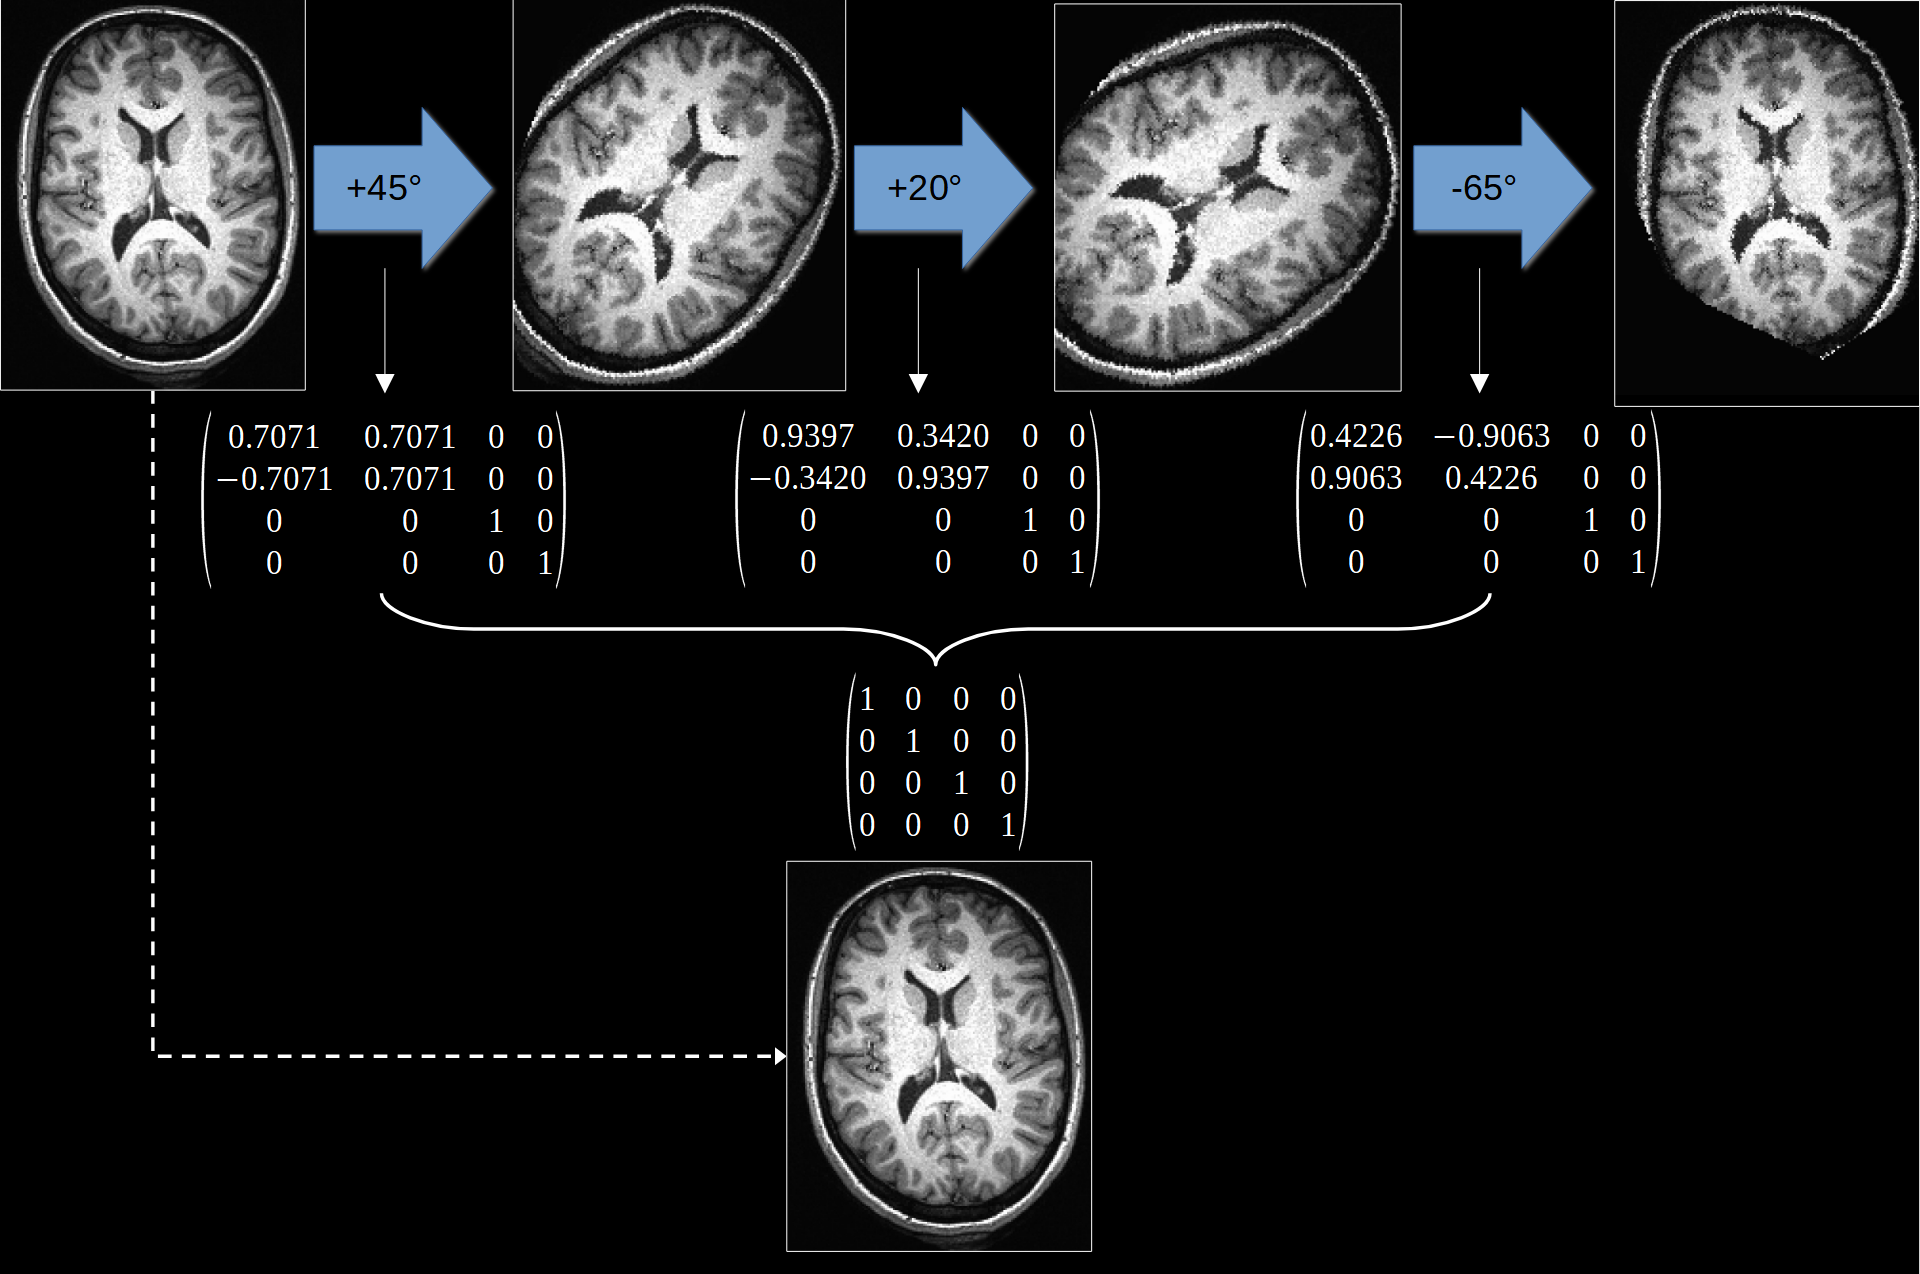

An illustration of this issue can be seen in Fig. 14. Here we can see how successive interpolation results in a loss of data and blurring of the image. The alternative is therefore to concatenate multiple transformations and then only resample the data once. In Fig. 14, concatenation reveals that that no changes are need and so no image degredation is necessary.

Fig. 14 Illustration of how applying multiple transformations can degrade a dataset. Instead, we can concatenate mutiple transformations together before applying them. In this example, the transformations cancel and thus no interpolation was actually necessary.#